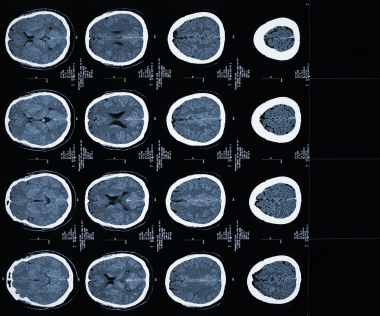

Провести клиническое обследование (анамнез и неврологический осмотр). Достоверная диагностика кровоизлияния в мозг возможна на основании КТ или МРТ томографии. При отсутствии возможности проведения этих методов, диагностика менее достоверна и является результатом анализа клинической картины, данных спинномозговой пункции (в ликворе присутствует кровь), эхоэнцефалоскопии, дуплексного сканирования и церебральной ангиографии. Также необходимо исследовать: электролиты сыворотки крови, показатели функции почек, ЭКГ, маркеры ишемии миокарда, клинический анализ крови, протромбиновый индекс, насыщение крови кислородом.

Медицинские процедуры, проводимые при заболевании внутримозговое кровоизлияние: КТ головного мозга (КПП) сканирование без красителей, Магнитно-резонансная томография, Спинальная пункция, Эхоэнцефалография, Дуплексное сканирование брахиоцефальных артерий (БЦА), Ангиография, Биохимический анализ крови, ЭКГ, Клинический анализ крови, Протромбиновое время, Протромбиновый индекс, Исследование газов крови